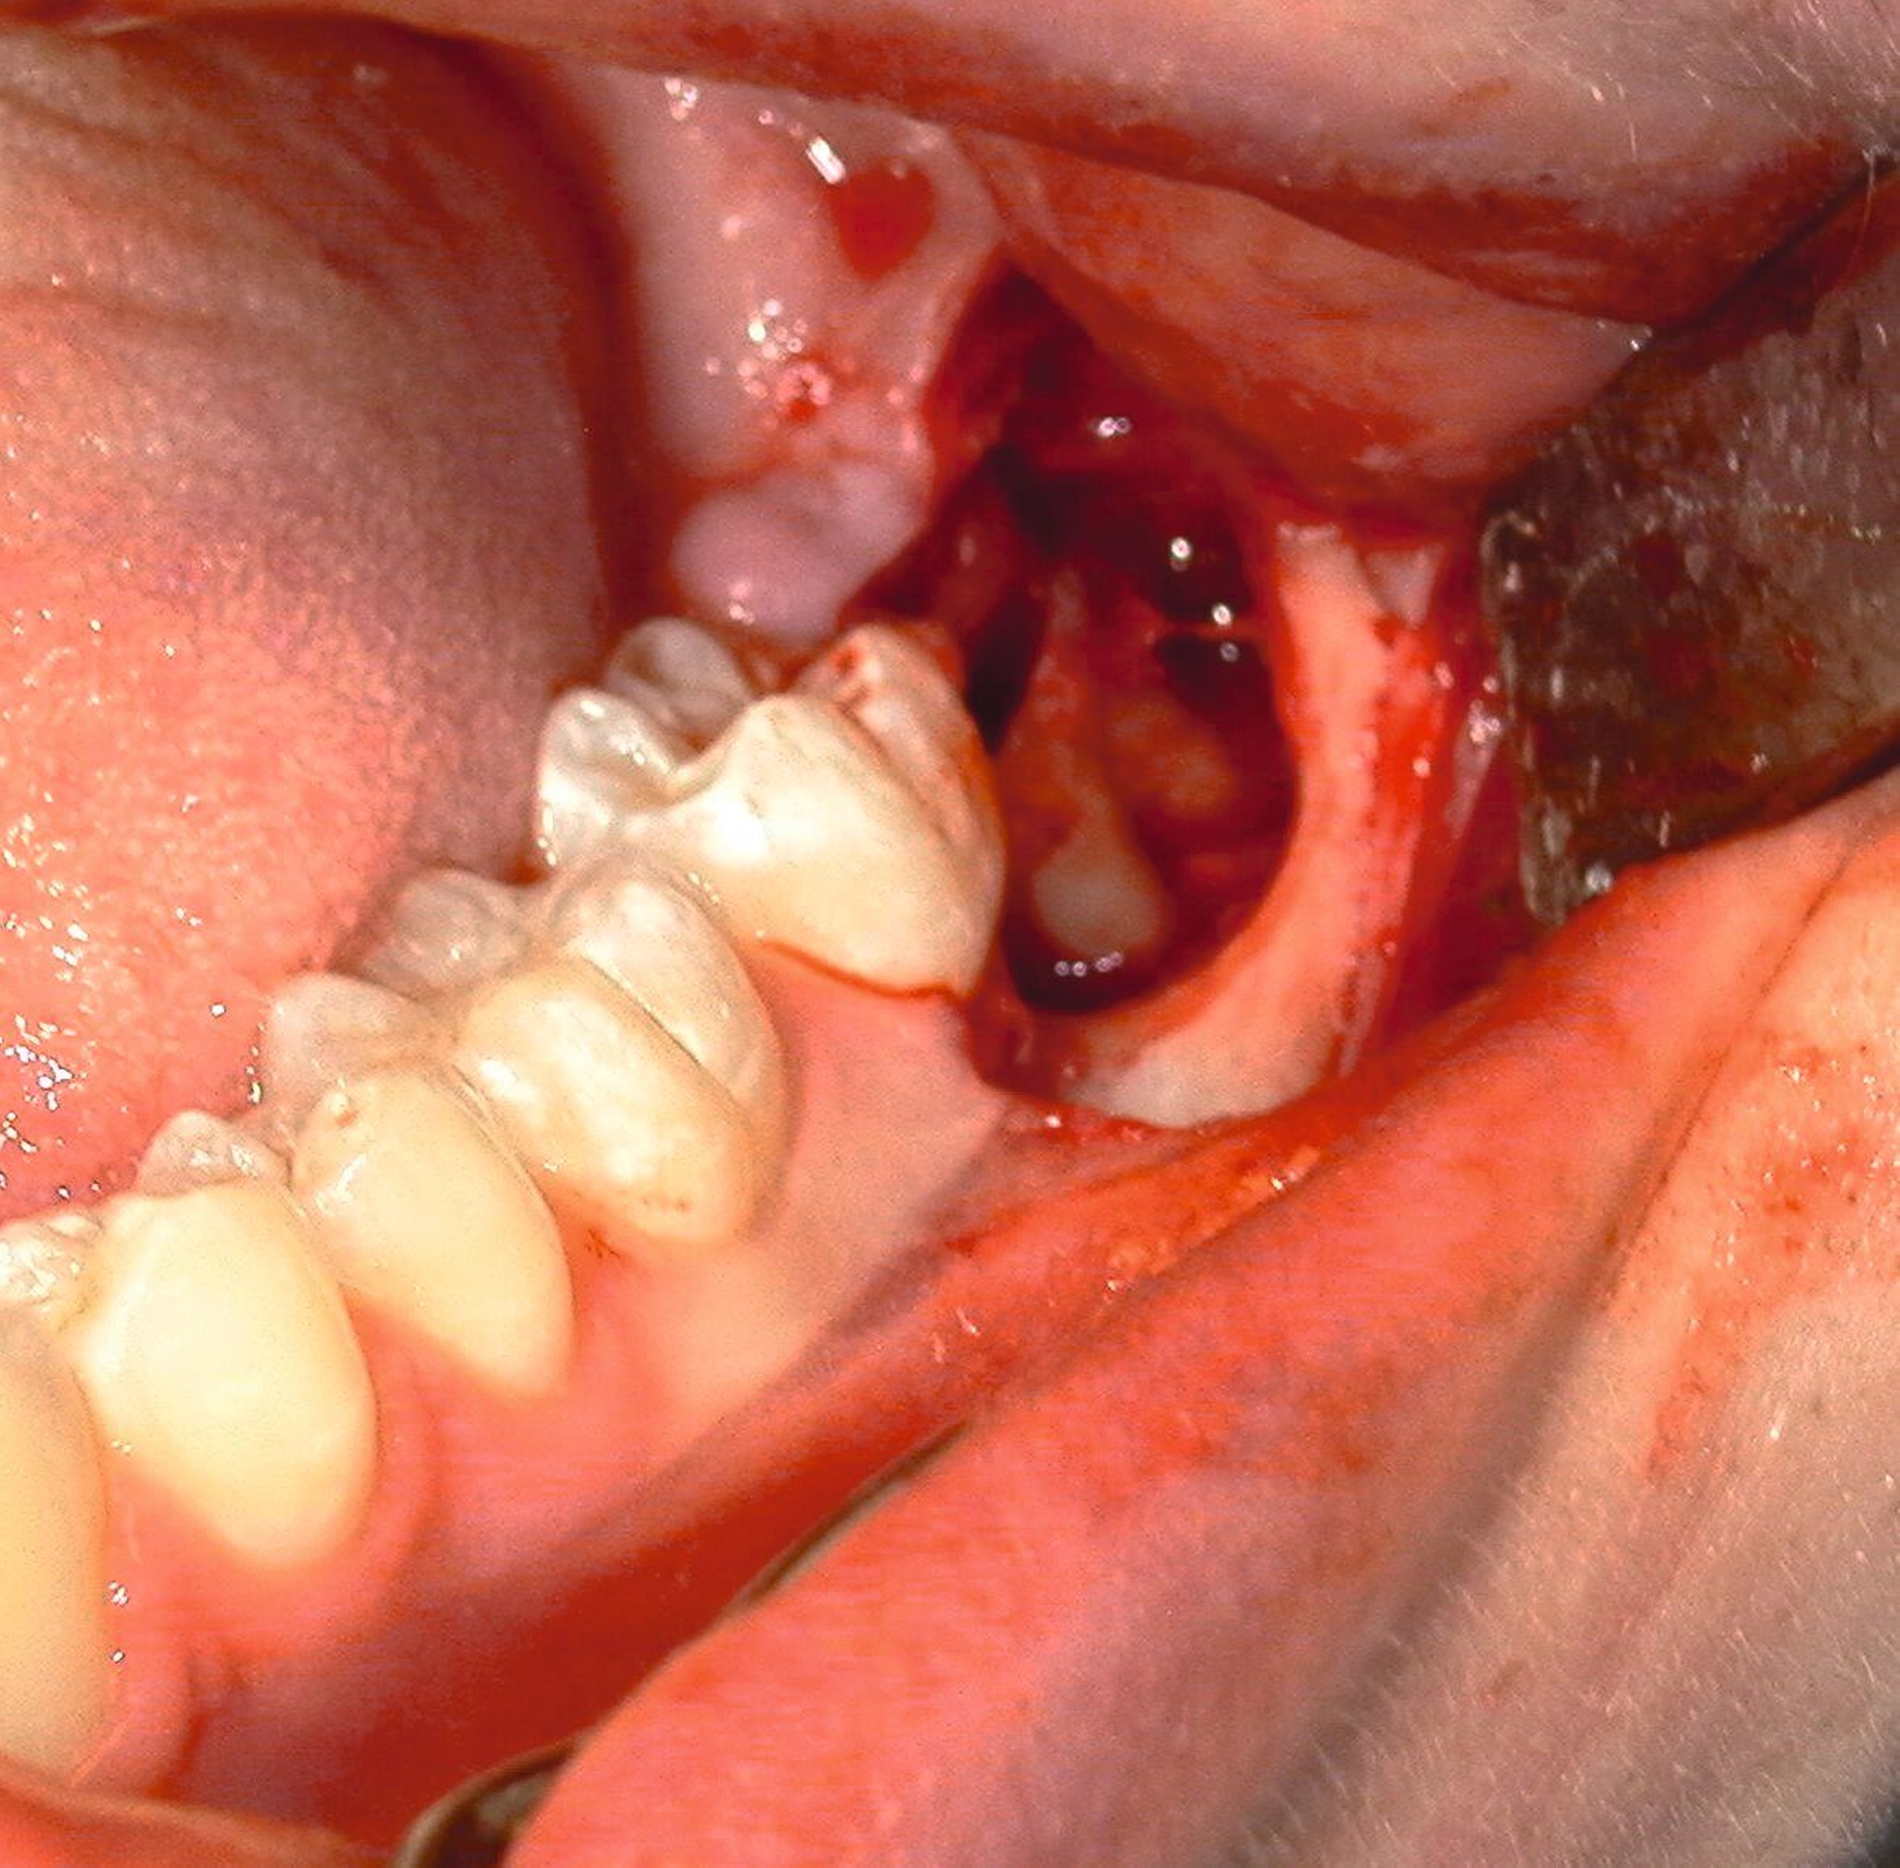

Anschließend erfolgt die sorgfältige Kürettage unter Schutz des am Boden der Extraktionsalveole liegenden Canalis mandibularis, die Entfernung von Granulationsgewebe sowie des Follikelepithels. Die Wurzelspitze sollte auf Vollständigkeit überprüft werden, um eine Wurzelfraktur auszuschließen (Abbildung 11).

Danach werden Knochenkanten geglättet und das Wundgebiet wird per Spülung sorgfältig gereinigt. Die Blutstillung kann mittels Kaustik oder Kompression durchgeführt werden [Gutwald et al., 2019]; Um die Wundheilung zu verbessern, kann man sich die Einlage von Hämostyptika oder autologen Thrombozytenkonzentraten zunutze machen [Vitenson et al., 2022].